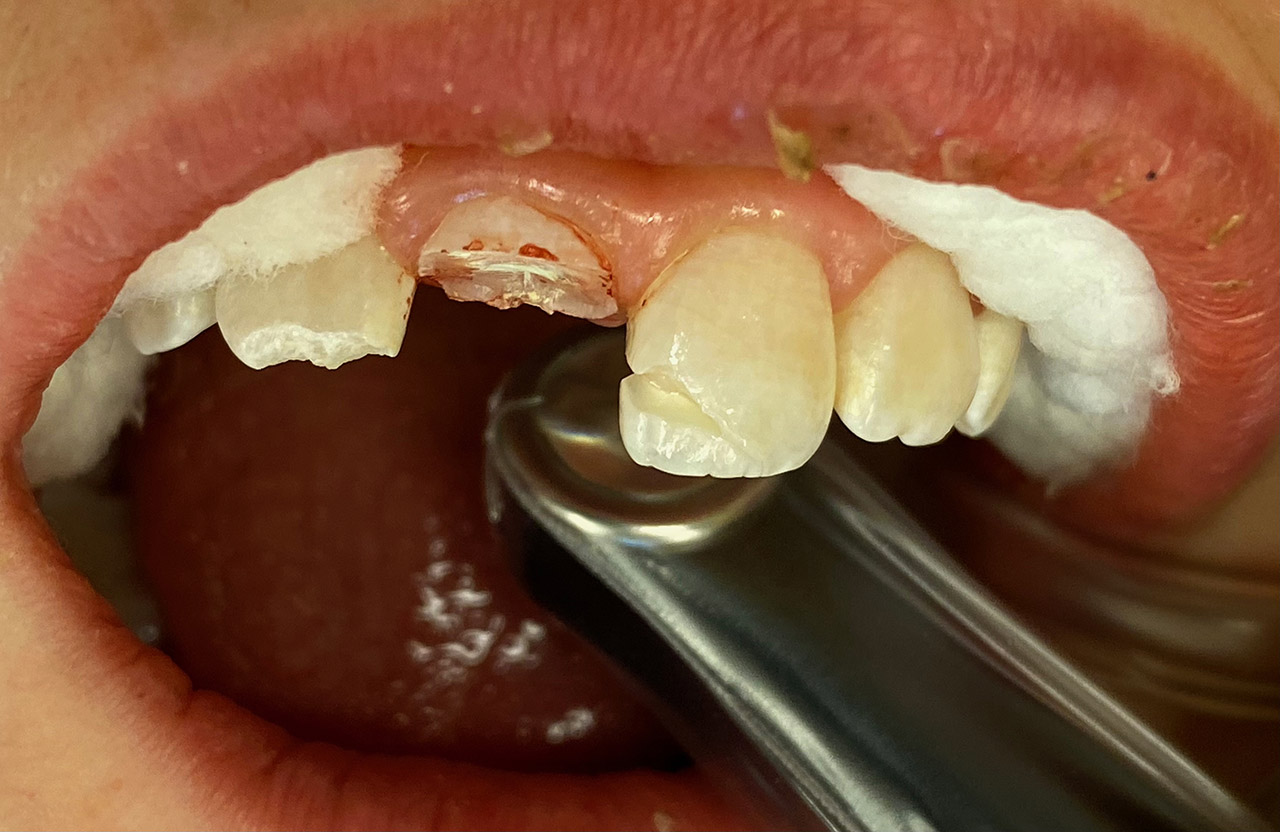

Traumatologie und Endodontie:

Nach Unfall/Sturz mittlerer Schneidezahn auf Gingivaniveau abgebrochen, Pulpa weit eröffnet, beide Nachbarzähne ebenfalls frakturiert.

Erstversorgung: Pulpektomie der Kronenpulpa, MTA, provisorischer Verschluß mit rosa Glasionomerfüllung.

Wiederaufbau der Nachbarzähne mit mitgebrachten (plus 1 Stein) Zahnstücken mit Kunststoff ergänzt und adhäsiv verklebt.